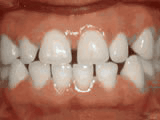

Open bite - Front teeth don't touch

Patient sucked her thumb as a young child. She started treatment at age 13. She had braces and a special appliance — called a crib — to retrain the tongue, for 28 months. Now she can bite the lettuce out of a sandwich.